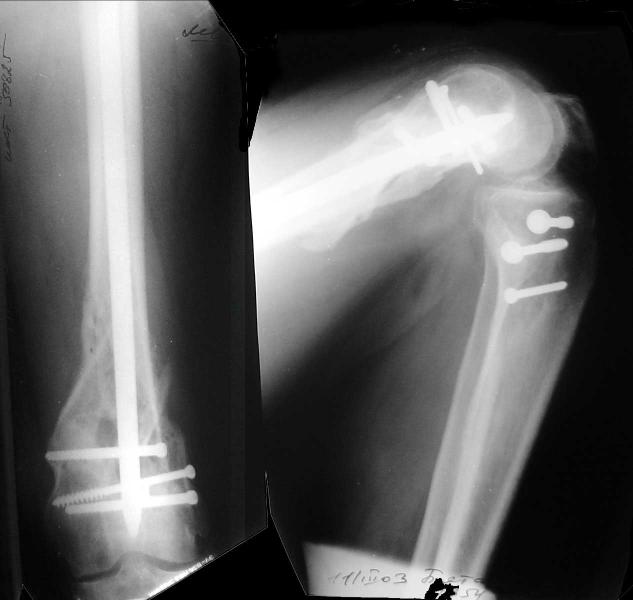

Re: Open supracondylar femur fx

And why LISS is superior here than nail?

Look what we would have done.